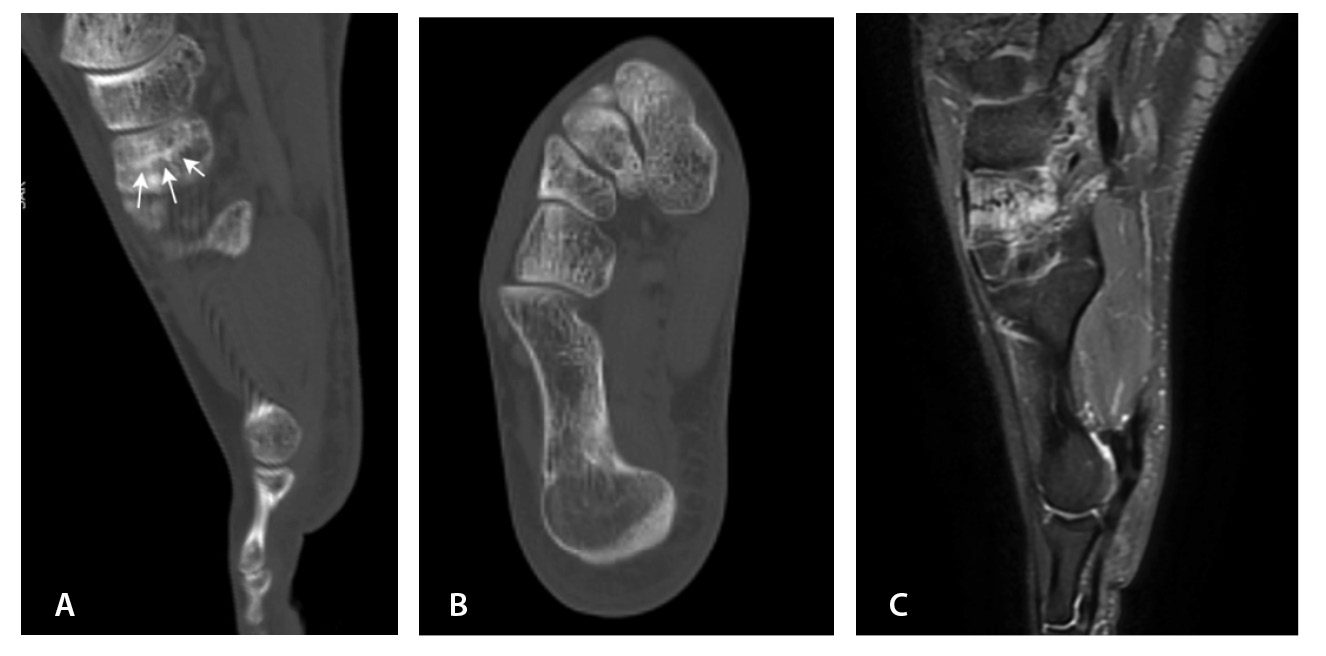

МРТ – первоначальный метод диагностики при подозрении на стрессовые переломы, так как ранним признаком таких переломов служит отек костного мозга пораженной кости, ярко выделяющийся среди остальных неизмененных костей. Отсутствие визуализации костного мозга затрудняет диагностику такого рода повреждений при рентгенографии и КТ (рис. 4). Чувствительность МРТ в выявлении стресс-переломов достигает 99% (95–100%), а специфичность – 97% (88–100%). Несмотря на то что исторически сцинтиграфия была основным методом обнаружения стресс-переломов с почти 100% чувствительностью, в настоящее время выполнение радионуклидного метода не рекомендуется из-за его низкой специфичности и высокой дозы ионизирующего излучения [54].

Рис. 4. Стресс-перелом промежуточной клиновидной кости: А – компьютерная томография (КТ), сагиттальная плоскость; Б – КТ, аксиальная плоскость; В – импульсная последовательность STIR, сагиттальная плоскость. Линия стресс-перелома слабо видна на КТ-изображениях, обнаруживается только при сагиттальных КТ-реконструкциях (стрелки). На изображениях магнитно-резонансной томографии отек костного мозга промежуточной клиновидной кости в режиме STIR ярко выделяется среди неизмененных костей